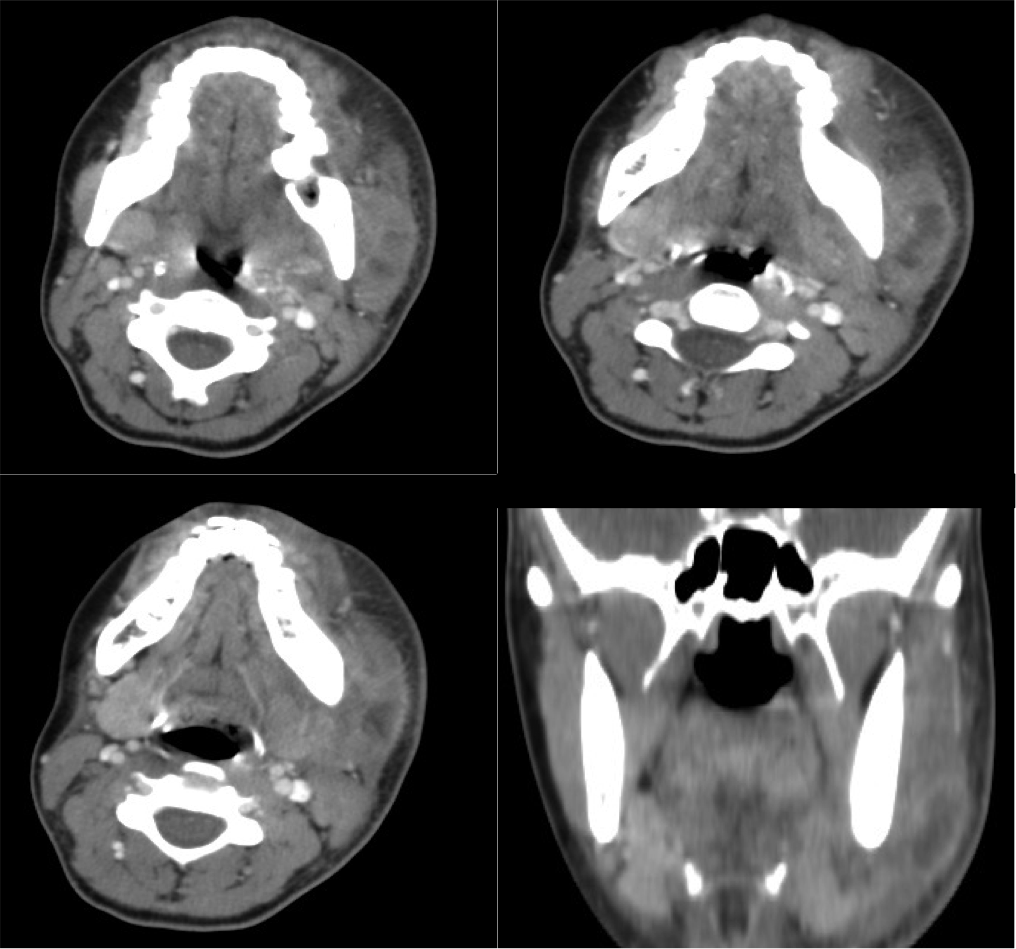

Angina de Ludwing:

No es un absceso, es una celulitis multiespacial ya que afecta al suelo de la boca y los espacios sublingual y submandibular. Se manifiesta clínicamente por dolor, hinchazón, disfagia, fiebre y elevación de la lengua, puede asociar crepitación si se deben a microrganismos anaerobios. En la TC con contraste se observa:

- Realce y edema difuso de los componentes del suelo de la boca.

- Debe determinarse si existe colección susceptible de drenaje, permeabilidad de la vía aérea y presencia de aire secundario al crecimiento de microorganismos anaerobios.

- La infección causa elevación y desplazamiento de la lengua que puede cerrar la vía aérea (debe tenerse en cuenta a la hora de manejar estos pacientes antes de realizar la prueba).